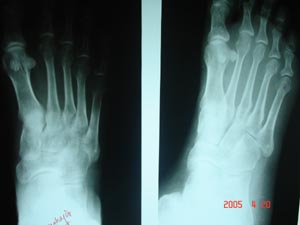

Fracture metatarsal

Fracture shaft of 5th metatarsal is visualized. With cancellous bone it may not be easy to recognize the fracture, unless it is seen on edges (break in cortex outline). But when any fracture is suspected & not seen in x ray re-examine after 10 days if symptoms still persists, a fracture line often becomes more obvious.